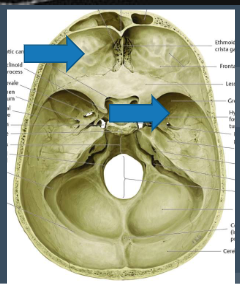

Identify the type of herniation indicated on the provided image: